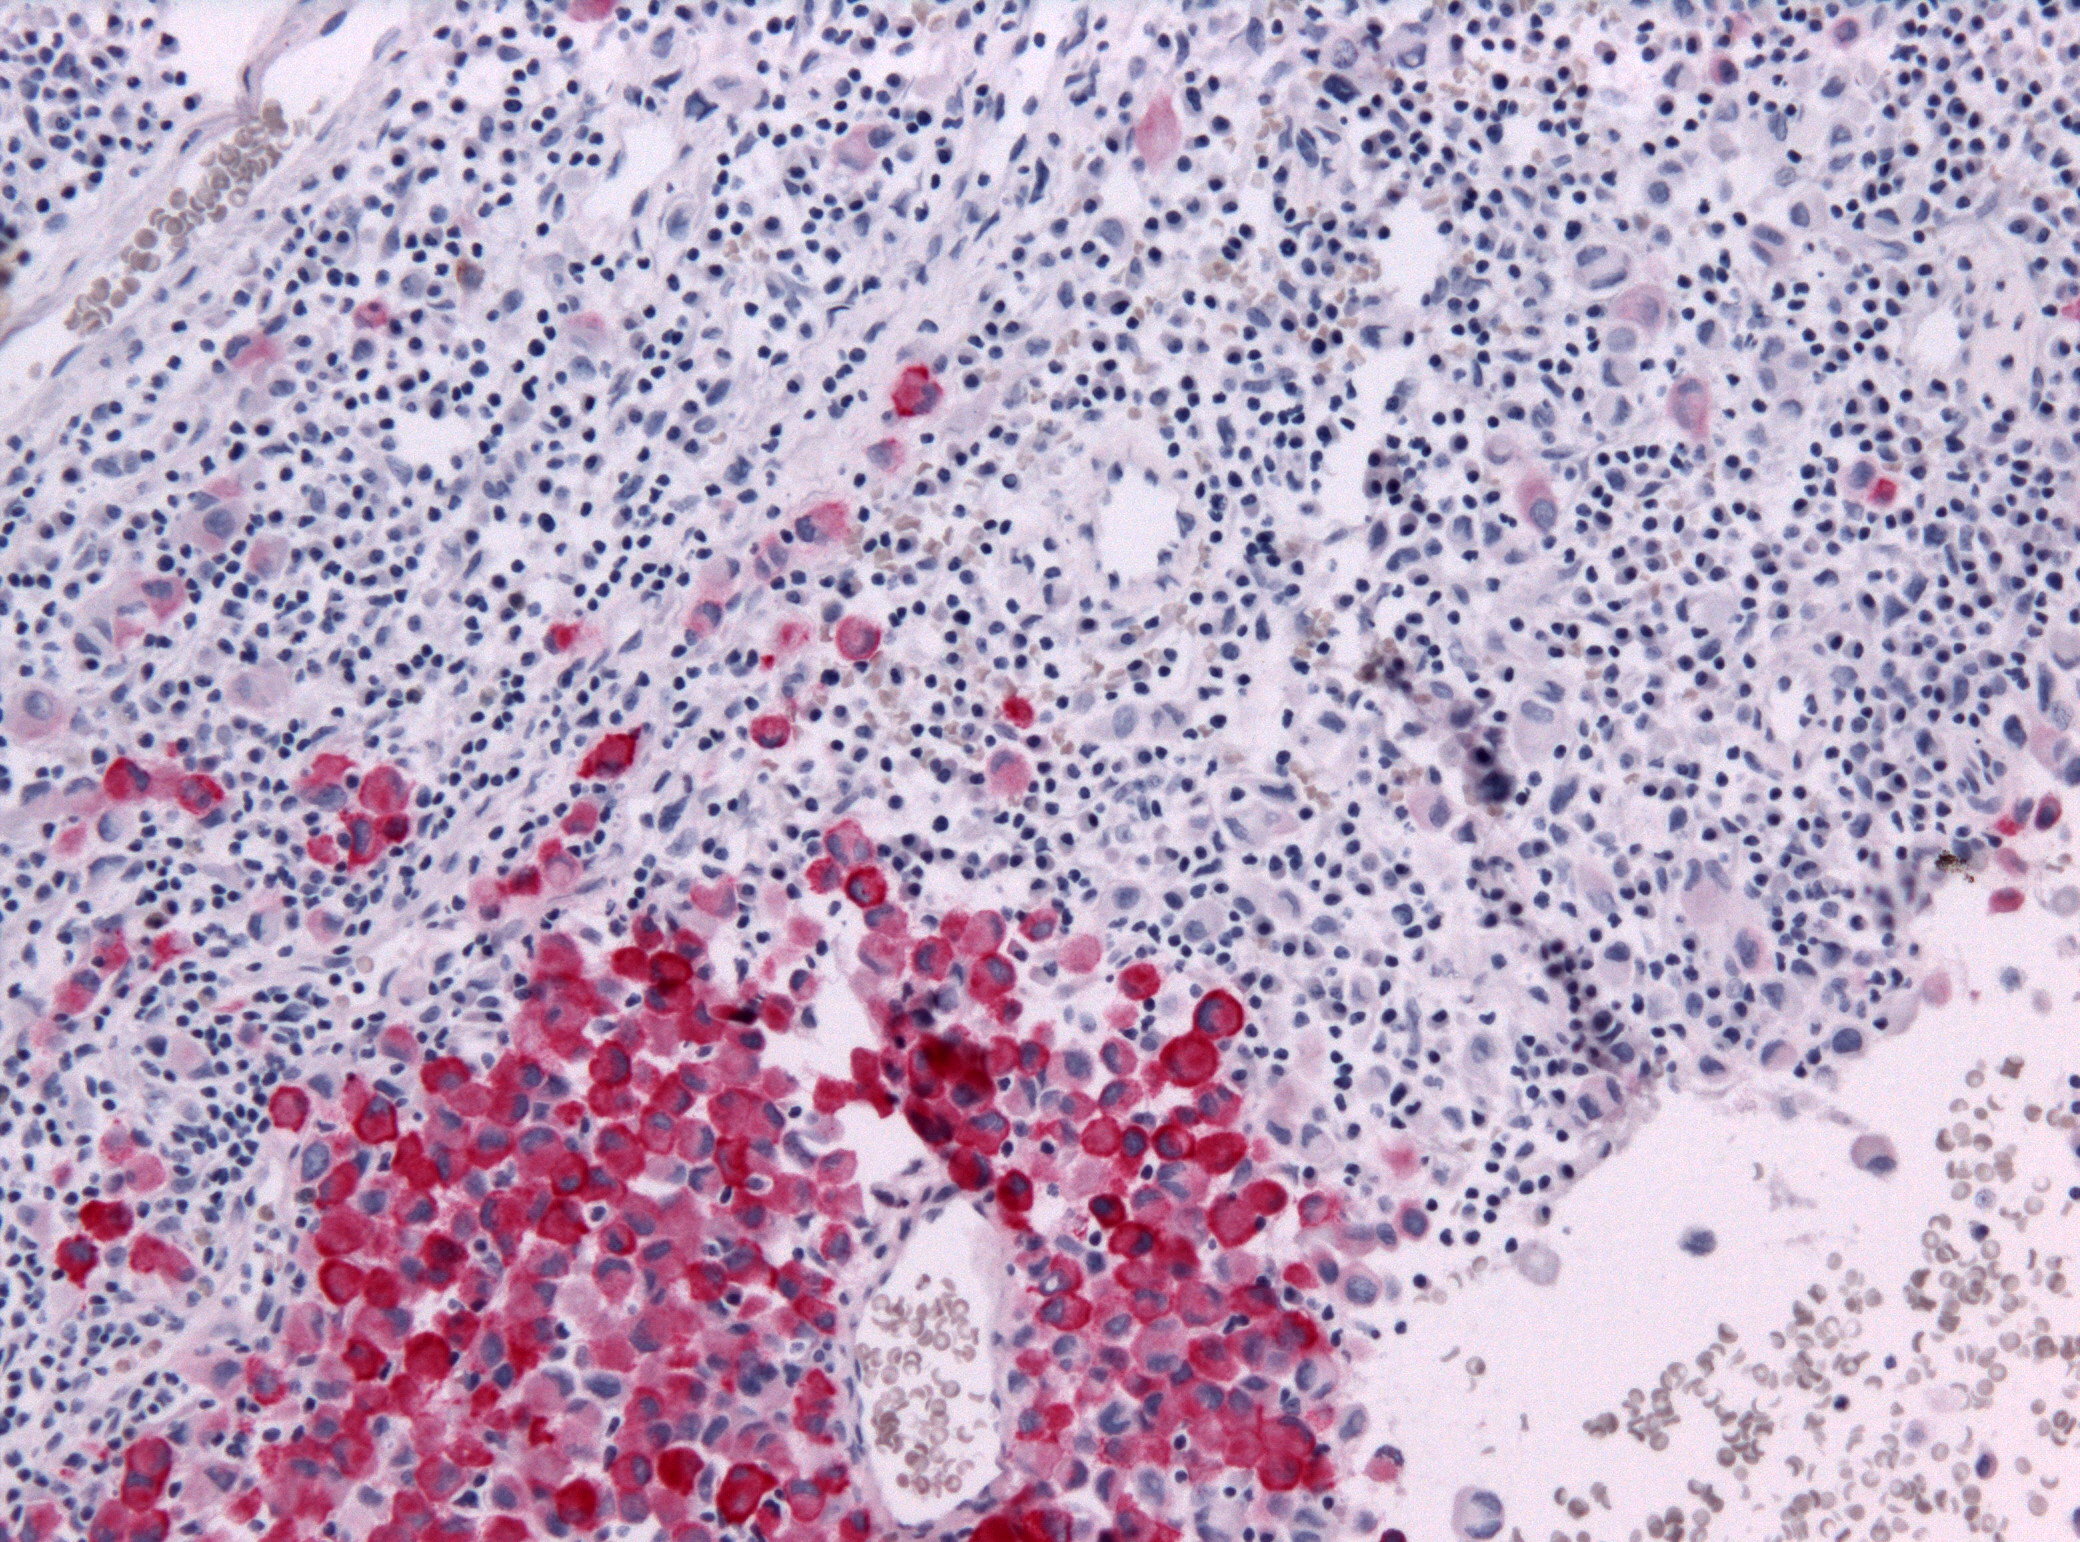

Jain, on the other hand, eager to be rid of the device, had her port removed immediately after finishing her chemo treatment. It’s as if by denying the port Jain wanted to deny her cancer; the port’s existence served to remind her that her body harbored an unnatural presence, a reminder that the cancer was also an unnatural invader. But while cancer may seem foreign enemy, it is an enemy from within, the ongoing process of cell regeneration gone berserk, violating the normal restraints with wild replication.

A study by the International Agency for Research on Cancer (IARC), part of the World Health Organization (WHO), reveals that in poor countries more people die of cancer than of AIDS, malaria, and tuberculosis combined. For years infections have resulted in liver and cervical cancer. But with enough economic development to permit more drinking, smoking, and consumption of fatty foods, the numbers of breast, colorectal, and lung cancer malignancies have grown. People consume things that aren’t good for them, and those in charge make the wrong decisions, often because they don’t know any better. While such cancers are often managed in affluent countries, the poor lackMalignant_melanoma facilities, awareness, and medications. Trained oncologists are rare in many parts of the world. Some languages don’t even have a word for cancer. People in pain don’t know the cause. Significant reductions in the spread of cancer can be achieved through certain vaccines, alternate medical procedures, reallocation of funds for research and drugs, and smoking cessation programs. In short, with information and policy changes, the cancer problem can be addressed, bringing the experience of cancer in poor countries to the level of that in the affluent. The main difference will be lower death rates and less pain because of drugs like morphine. Still, as populations age the incidence of cancer will grow.